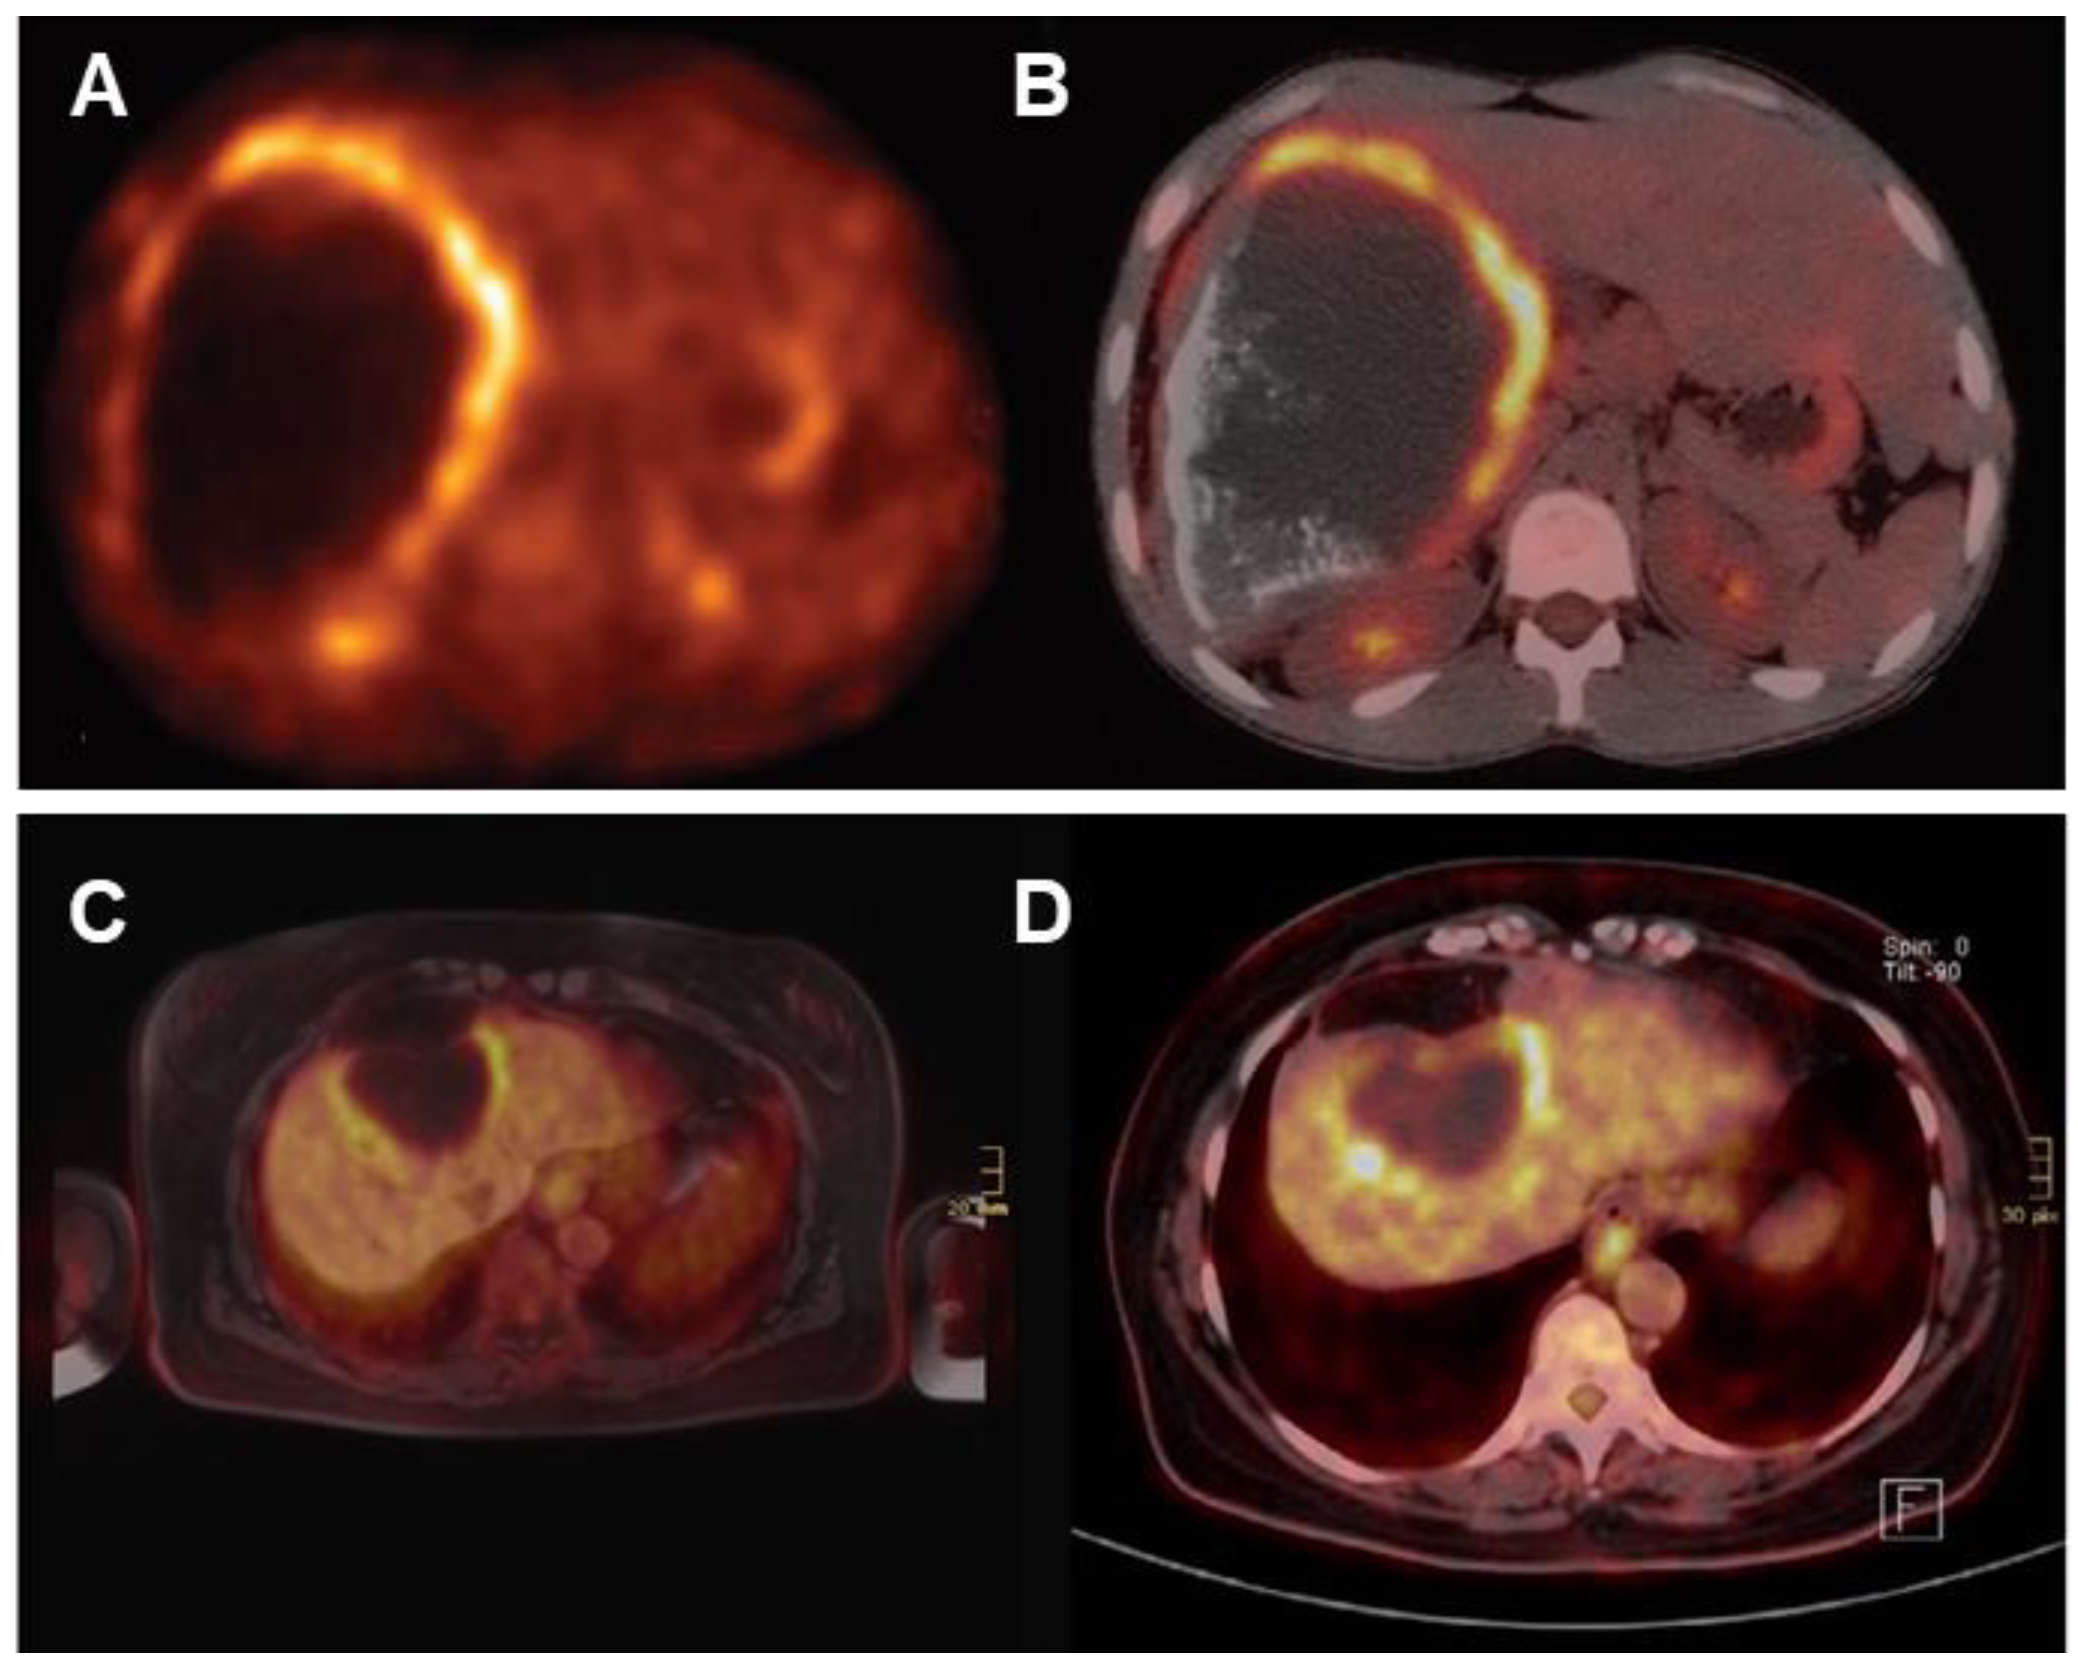

FDG-PET is also used for long-term follow-up of AE (Figure 10). The absence of metabolic activity indicates suppression of parasite activity, which is not equivalent to parasite death. This suppression can persist for several years, and oral medication therapy should be reinitiated when recurrence is detected by PET [167,168,169]. In a retrospective study of 179 AE patients who underwent PET/CT scans, it was found that as the clinical status progressed, significant changes occurred in total immunoglobulin E (IgE), parasite-specific IgE, and serological status (using crude antigen preparations or recombinant/purified antigens such as EM10, Em18, and Em2) [170]. Notably, these serological biomarkers were also significantly higher in patients with positive PET results. Multiple studies have shown that combining FDG-PET with serological testing can further improve the accuracy of parasite activity identification [171]. For patients with AE who are unable to undergo surgical resection, oral albendazole treatment is often prescribed; the treatment usually is life-long. For patients with inactive disease, a structured treatment interruption (STI) of drug therapy may be a goal, not only to save costs but also to improve quality of life. Ammann et al. [172] evaluated FDG-PET/CT and antibody levels against recombinant Emll/3-10 antigen as markers of parasite vitality, serving as a reliable tool to allow for the selection of patients who can safely discontinue chemotherapy with a low risk of AE recurrence. Husmann et al. [173] hold the view that negative FDG-PET/CT results combined with no detectable levels of Em-18 antibodies may allow for the safe discontinuation of benzimidazole therapy in patients with AE. The quantitative imaging parameter SUVratio, obtained through PET/CT, correlates with the time to reach no detectable levels of Em-18 antibodies and the duration of benzimidazole treatment. In patients presenting negative results for both indicators, a watch-and-wait strategy might be permissible [174].